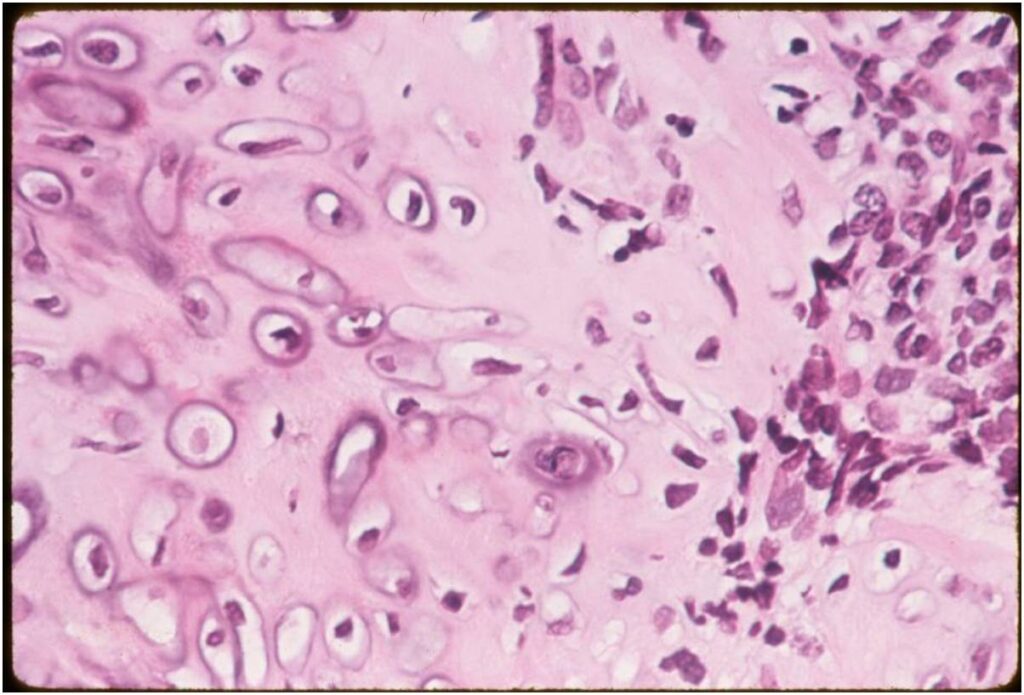

- Low grade islands of cartilage scattered throughout the mesenchymal cells

- Usually only a small part of lesion

- Cytologically low grade

- Usually sharply demarcated from surrounding stroma

- Cells within cartilage

- Tend to have round or ovoid nuclei

- Lacunae are poorly formed

(Right Arrow) Cartilaginous Component